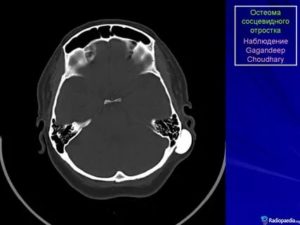

При проведении КТ височных костей (Рисунок 2) справа визуализировалось костное образование на широком основании на задне-нижней стенке НСП, имеющее внутри себя воздушную полость с тонкой костной стенкой, граничащую с клетками сосцевидного отростка. Медиальнее образования имелось мягкотканое затемнение (предположительно слущенный эпидермис и ушная сера).

В свою очередь, барабанная полость и клетки сосцевидного отростка оставались абсолютно воздушными, что с высокой долей вероятности свидетельствовало о целостности барабанной перепонки.